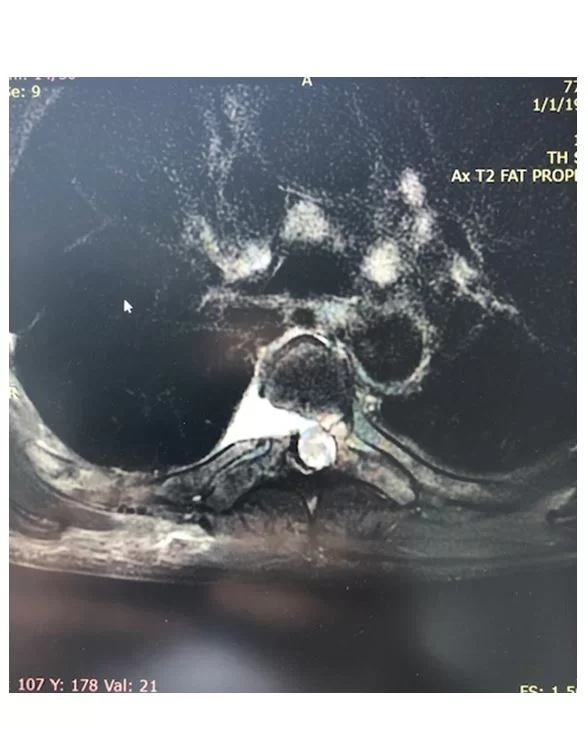

Διαθωρακικά: Δηλαδή με τη βοήθεια θωρακοτομής. Σ’ αυτή την περίπτωση η προσπέλαση γίνεται μέσα από τον θωρακικό κλωβό, δηλαδή ανάμεσα από τα πλευρά του θώρακα (Εικόνα 2 και 3).

Οπισθοπλάγια προσπέλαση: Αυτή η προσπέλαση λέγεται και πλευρεγκαρσιεκτομή. Ο χειρουργός έχει πρόσβαση μέσω μιας τομής στο πίσω μέρος της σπονδυλικής στήλης. Στη συνέχεια δημιουργείται ένα παράθυρο μέσα από τα οστά που καλύπτουν την κήλη, αφαιρώντας ένα μικρό μέρος της πλευράς, στο σημείο όπου συνδέεται με τη σπονδυλική στήλη.